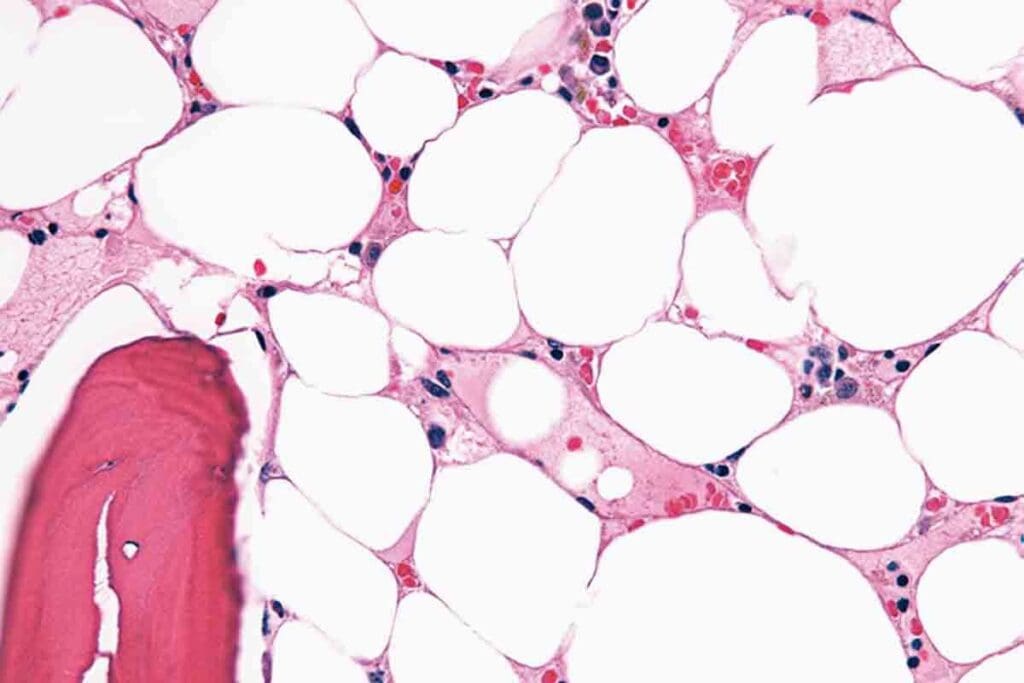

Aplastic anemia is a rare and serious condition where the bone marrow fails to make blood cells. This failure means the bone marrow can’t produce enough red blood cells, white blood cells, and platelets. This leads to pancytopenia.

Aplastic anemia happens when the bone marrow can’t make blood cells. Normally, the bone marrow turns stem cells into different blood cells. But in aplastic anemia, this process stops, causing a lack of blood cells.

- Bone marrow biopsy, a key test to see if the bone marrow works right.

The bone marrow biopsy is very important. It lets doctors see if the bone marrow can make blood cells.

Aplastic anemia is when the bone marrow can’t make enough blood cells. This isn’t because of too many cells growing. It’s because the bone marrow isn’t working right.

The pre-transplant evaluation includes many tests. These tests check the patient’s health and the severity of their aplastic anemia. They also include blood counts and bone marrow biopsies.